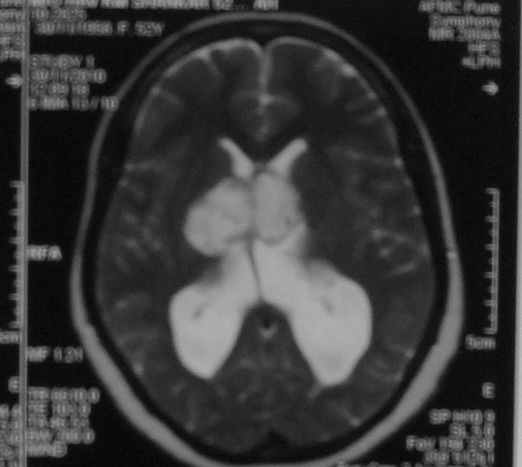

Hydrocephalus

Hydrocephalus is a common problem in the childhood, due to obstruction to the flow of cerebrospinal fluid (‘clear fluid within the brain cavities’). Child presents with an enlarging head, headache, vomiting, drop in school performance. MRI is required to diagnose hydrocephalus, and to ensure that there is no brain tumor causing obstruction. Treatment is insertion of ventriculoperitoneal shunt from brain to the abdomen. In older children, endoscopic third ventriculostomy too can be considered.